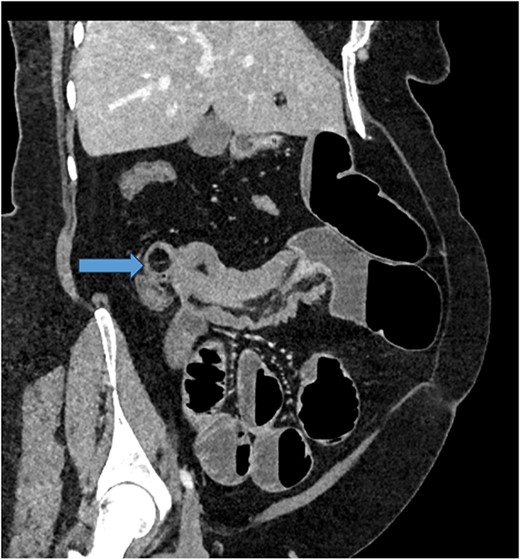

Given her abdominal symptoms and signs, she was subjected to an abdominal X-ray (Fig. 1), which showed multiple distended loops of the small bowel, and a chest X-ray, which showed left basal atelectasis. A working diagnosis of SBO was made. She was put nil by mouth. A nasogastric tube and a urinary catheter were inserted. After initial resuscitation, she was subjected to CTAP with contrast. The findings of the CTAP were in keeping with acute distal SBO secondary to an ileo-ileal intussusception. No obvious mucosal mass was stated in the initial report (Figs 2 and 3).

CT scan of abdomen: oblique coronal view of abdomen showing intussusception with low attenuation lesion distally C/W a lipoma (arrow).

CT Abdomen: MPR reconstruction of the plane of intussusception showing a distal lipoma and proximal start of intussusception.